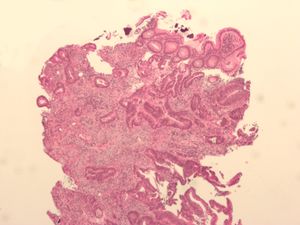

Micrograph of a colorectal villous adenoma. These lesions are considered pre-cancerous. H&E stain.